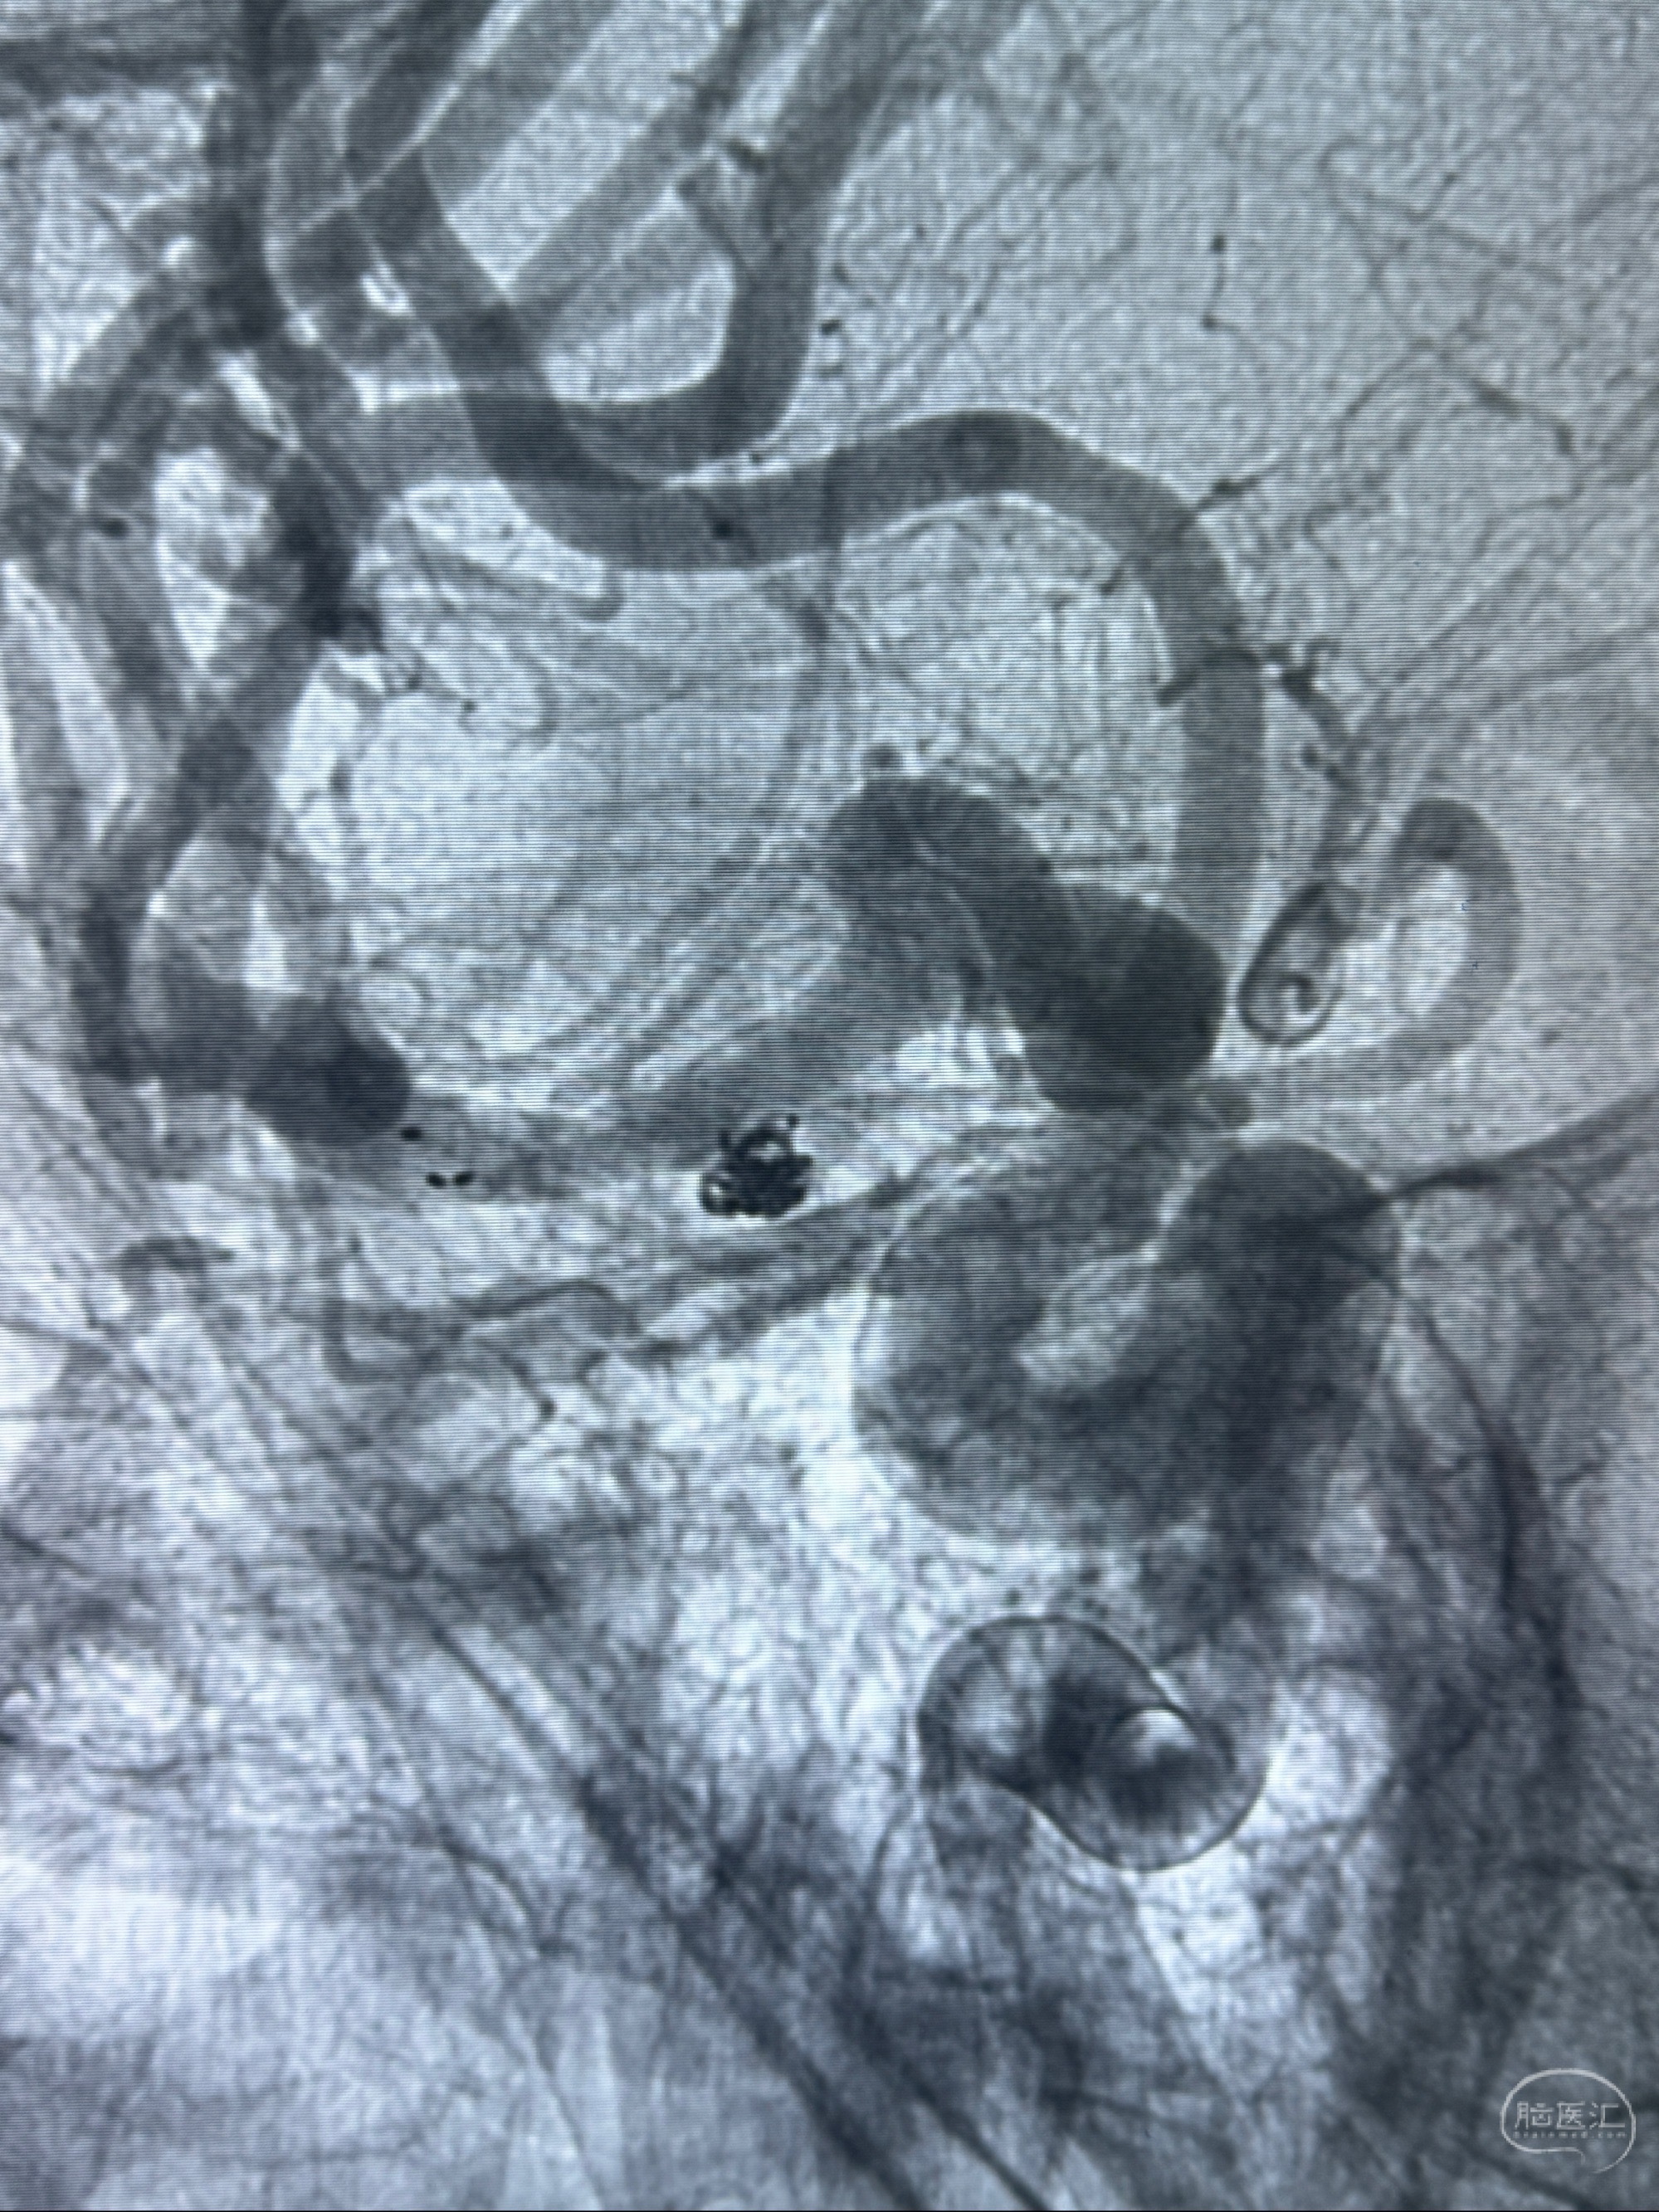

2023-12-04全麻下行支架辅助治疗

S-AB4-20mm

麻醉苏醒佳,遵嘱动作